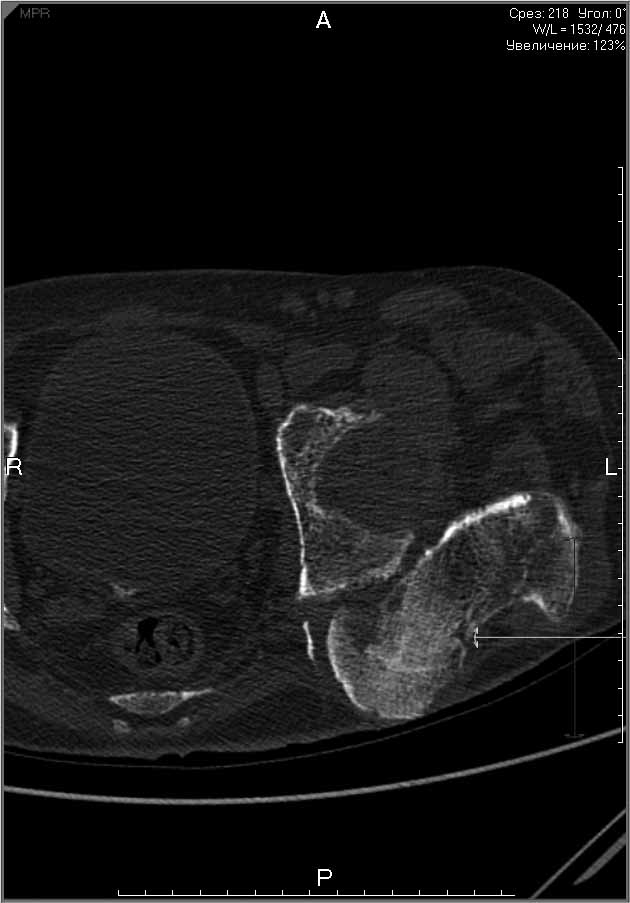

Пациенту 22 года. Травма в июле 2010г, лечился в районной больнице. К нам попал в апреле 2011г.Тяжелая сочетанная травма (29.07.2010): тупая травма живота с повреждением внутренних органов. Закрытая травма грудной клетки с переломом ребер. Пневмоторакс справа. Тяжёлая позвоночно-спинномозговая травма. Закрытый осложнённый переломо-вывих С5 позвонка. Верхний парапарез, нижняя параплегия, нарушение функции тазовых органов по типу недержания. Цекостома. Пролежень левой ягодичной области. Неправильно консолидированные переломы верхних третей обеих бедер. Застарелый вывих левого бедра.Осложнение: Поддиафрагамльный абсесс слева, забрюшинного пространства. Свищ желудка и ободочной кишки. Синегнойный сепсис. Двухстороняя пневмония. Но это уже анамнез.Пациент был неоднократно оперирован на органах брюшной полости и осложнениями с ними связанными.

В ягодичной области слева глубокий пролежень размером 2х2см, дном является вывихнутая головка бедра. Неврологически в нижних конечностях динамика положительная, появились движения в правой стопе, чувствительность в стопах.По переломам бедер: подвижности в местах переломов нет, снимки высылаю.

Планирую начать с правого бедра, ЧКО таза (передняя рама) с фиксацией бедра. О/клазия места перелома правого бедра и устранение грубых смещений в аппарате. окончательно можно оставить и в аппарате. Далее аппаратное устранение вывиха левого бедра.